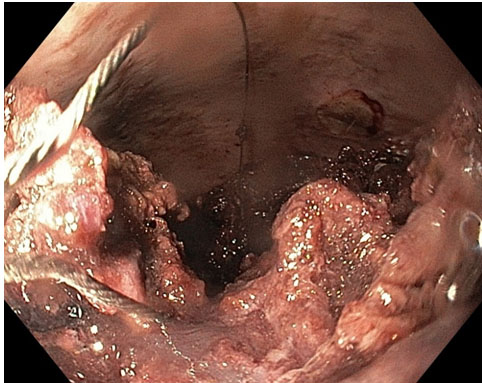

Gastroscopy was done under general anesthesia. In this procedure a gastroscope (GIF-H190; Olympus, Center Valley, PA, USA) and an esophageal overtube were used (Guardus Overtube; Steris, Mentor, OH, USA). Gastroscopy found a large amount of food bolus and blood clot in the dilated esophagus precluding further advancement of the gastroscope. The gastroscope was removed, and an overtube was fitted. The scope and overtube were then reinserted via the mouth and advanced to the esophagus to facilitate repeated passages of the scope. There was a large amount of organized clot and food in the entire esophagus. Due to this scope passage to the lower esophagus was not possible. Large clots with food were snared, suctioned, and manipulated to allow reasonable capture in repeated Roth Net passes (Figure 1). A combination of endoscopic suction, irrigation, snare use, and Roth Net use provided little improvement in clearance. Hence a nasogastric (NG) tube was inserted via the overtube into the oesophagus under direct visualization being following by the gastroscope (Figure 2). With adequate lubrication, the overtube can easily accommodate the standard gastroscope and an NG tube (Figure 3). The NG tube was connected to wall suction. The NG tube can be manipulated back and forth controlled at the site of insertion in the overtube to ensure adequate and—to some degree—targeted suction. With a combination of endoscopic irrigation and direct high suction with the NG tube, the food and clot were broken down and cleared effectively.

Figure 2: Endoscopic image showing irrigation and NG tube (seen at 1 o’clock) suction to clear the esophagus.